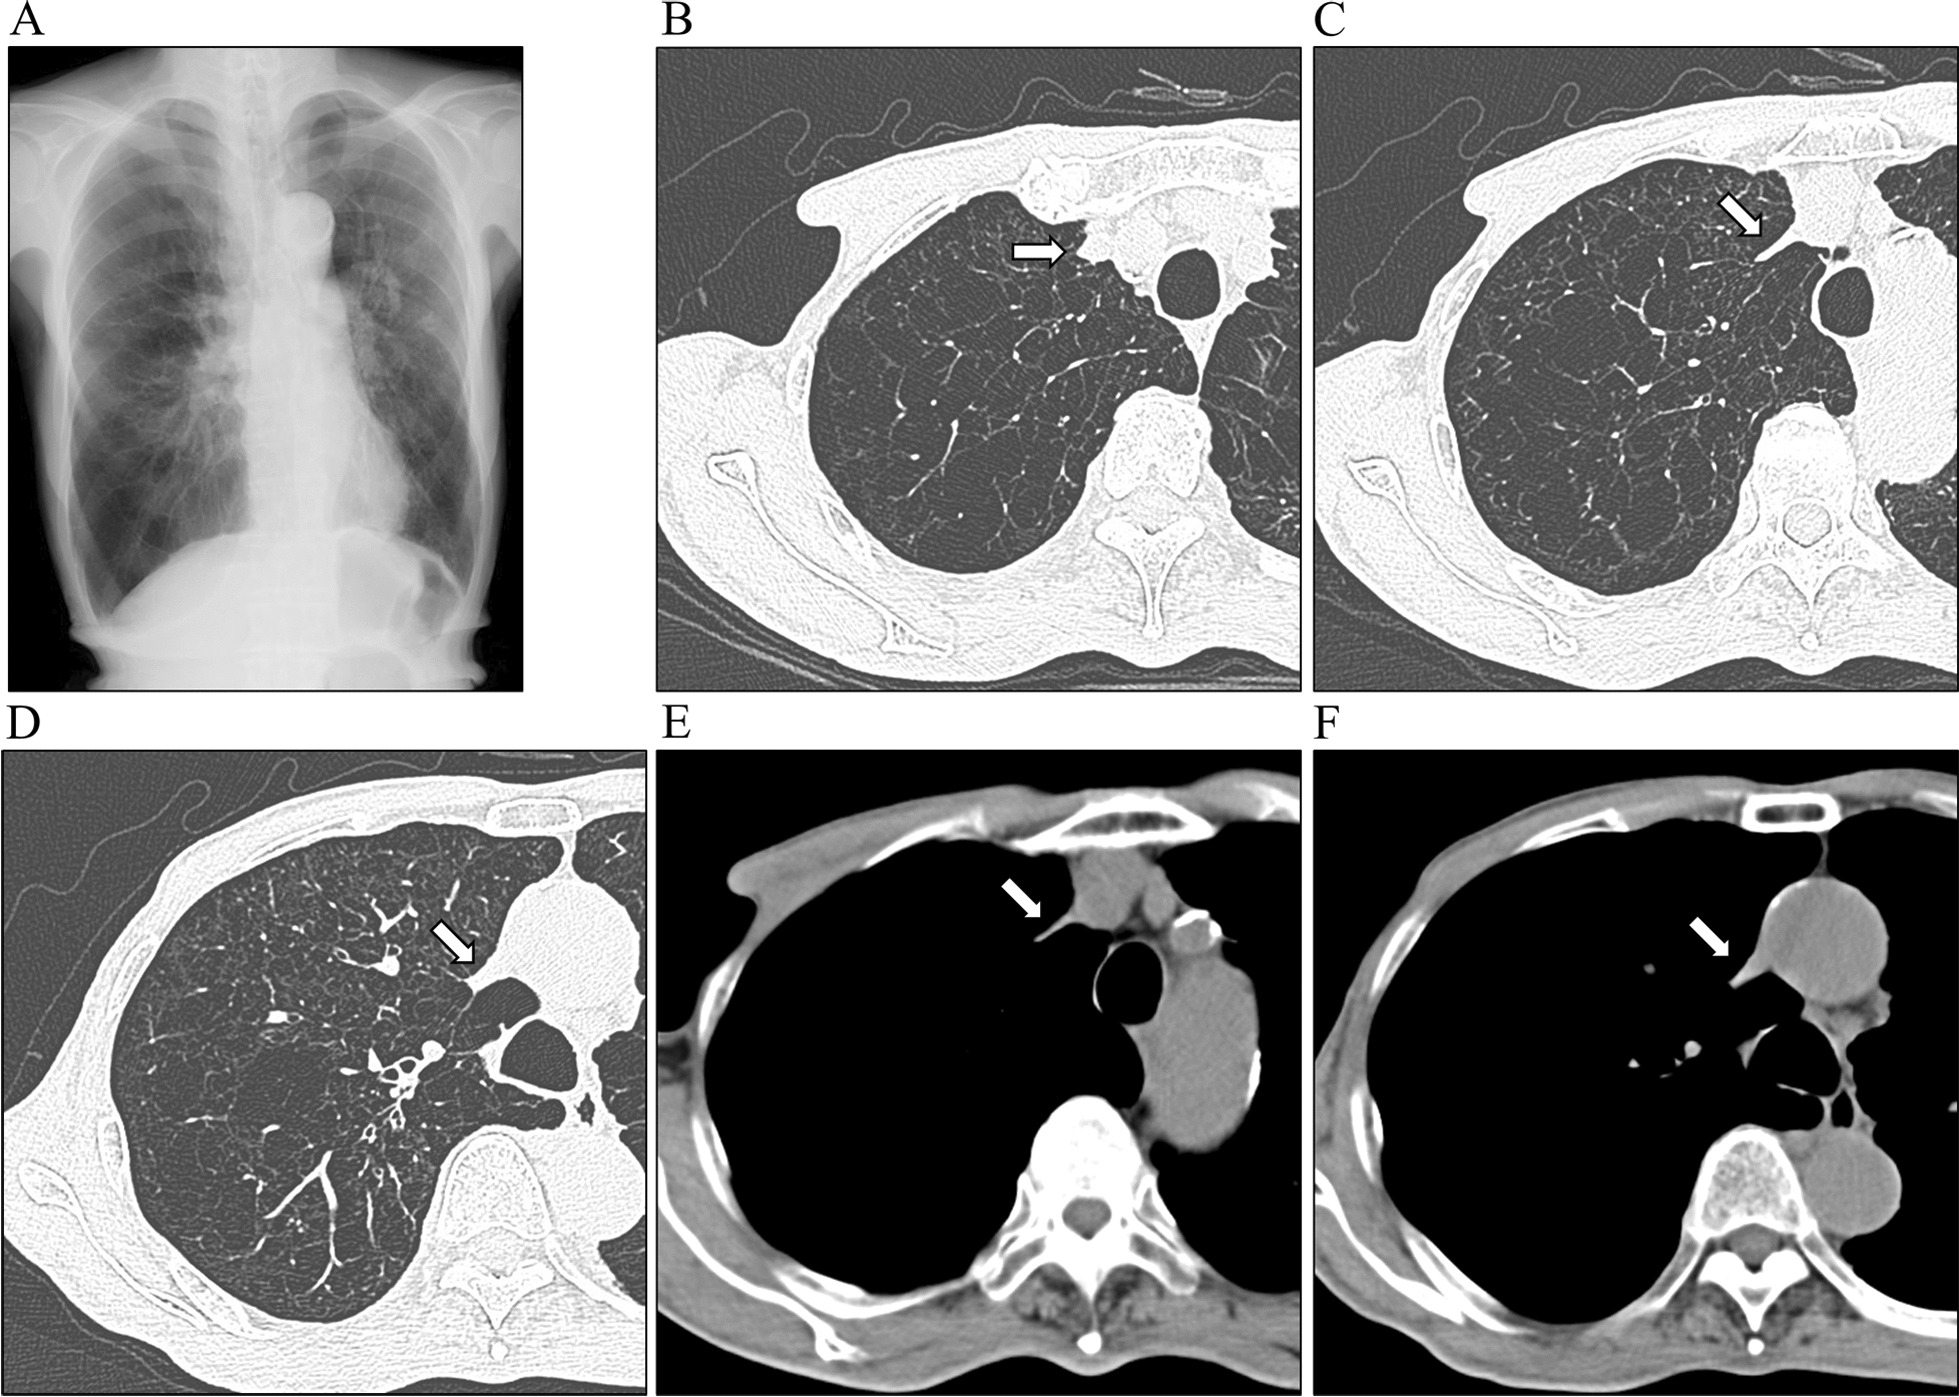

Fig. 2.

A Chest X-ray showing hyperinflation of the lung field. B–F Chest computed tomography showing emphysematous change. Arrows indicate the superior vena cava, which is partly extremely narrow

An 82-year-old Japanese man presented to the hospital with a history of progressive dyspnea on exertion (mMRC grade 2) that had been ongoing for several years. He had worked as a fisherman and had been a one-pack-a-day cigarette smoker for over 50 years. He never consumed alcohol and had no previous history of malignancies or cardiovascular diseases. He has no history of catheterization such as central venous catheters or irradiation. Upon examination, his height measured 164.7 cm and he weighed 48.5 kg, resulting in a body mass index of 17.9. He was found to have pursed-lips breathing with hypertrophic sternocleidomastoid muscles. However, there were no noticeable signs of swelling in his neck, face, or upper extremities (Fig. 1A). Additionally, we observed intercostal enlargement and reduced thoracic movement during respiration. Small vascular dilatations were visible on his chest and upper abdomen (Fig. 1B), with blood flow noticed in the direction of head to leg, a characteristic sign of SVC syndrome. Chest radiography revealed hyperinflation with a drop-like appearance of the heart (Fig. 2A), while CT scans depicted extensive emphysematous changes (Fig. 2B–F). Notably, the SVC exhibited partial narrowing in a slit-like configuration (Fig. 2C, indicated by arrow). No mass lesions compressing the SVC were identified in the lung fields or mediastinum, and there were no giant bullae adjacent to the SVC. Pulmonary function testing yielded the following results: vital capacity (VC) of 2.88 (88.3% of the predicted value), forced expiratory volume in one second (FEV1) of 0.82L (44.4% of the predicted value), FEV1% (FEV1/forced VC) of 31.29%, and fractional exhaled nitric oxide level of 14 ppb. The blood D-dimer level was within normal range, indicating an absence of thrombotic occlusion. Hemoglobin in the blood was 11.8 g/dL. Arterial blood gas analysis demonstrated a pH of 7.419, PaCO2 of 40.8 mmHg, and PaO2 of 57.8 mmHg. As a result, the patient received a diagnosis of COPD. He was started on a long-acting muscarinic antagonist and a long-acting beta-2 agonist. After 3 months, there was a slight improvement in his dyspnea. However, physical examination findings related to SVC syndrome remained the same, and the narrowing of the SVC persisted on CT images (not shown).